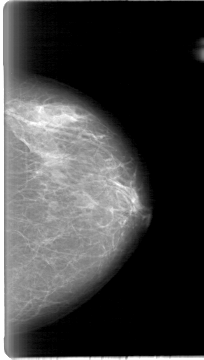

D_4015_1.LEFT_MLO

LEFT_MLO LINES 5386 PIXELS_PER_LINE 3241 BITS_PER_PIXEL 12 RESOLUTION 43.5 NON_OVERLAY